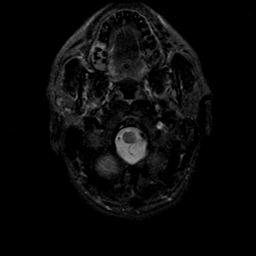

MR Study #21, November 3, 1991 -- Slice #2

[Home][Help][Clinical][Tour 1][Tour 2] Slice 2